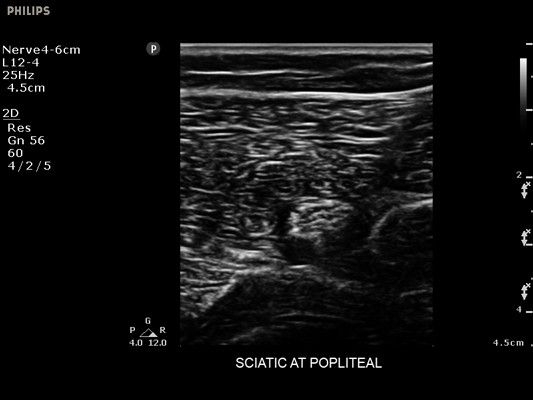

• Диагностика нервов

• Линейный УЗИ датчик Philips L12-4